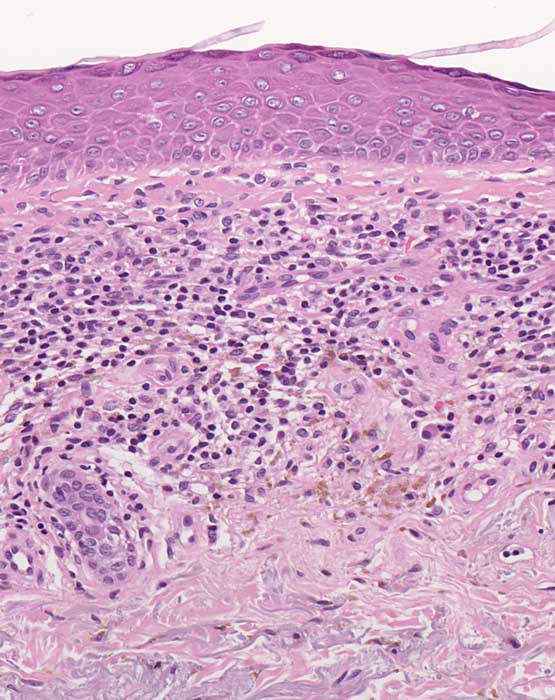

PathoPic – image database / PathoPic ID 6933 - Purpura pigmentosa progressiva (Morbus Schamberg)

Purpura pigmentosa progressiva (Morbus Schamberg)

Oberflächlich perivaskuläre Lymphozyten und Plasmazellen. Vereinzelt Erythrozytenextravasate. Zahlreiche Siderophagen. Keine Vaskulitis.

Punktförmige Petechien symmetrisch von den Unterschenkeln aufsteigend. Konfluenz zu bräunlichen Plaques. Kein Juckreiz.

Der Morbus Schamberg gehört zur Gruppe der hämorrhagisch pigmentären Dermatosen, die charakterisiert ist durch Erythrozytenextravasate und Hämosiderinablagerungen. Im Gegensatz zur Stauungsdermatitis sind die Hämosiderinablagerungen bei den pigmentären Dermatosen oberflächlicher.

Histologie

200